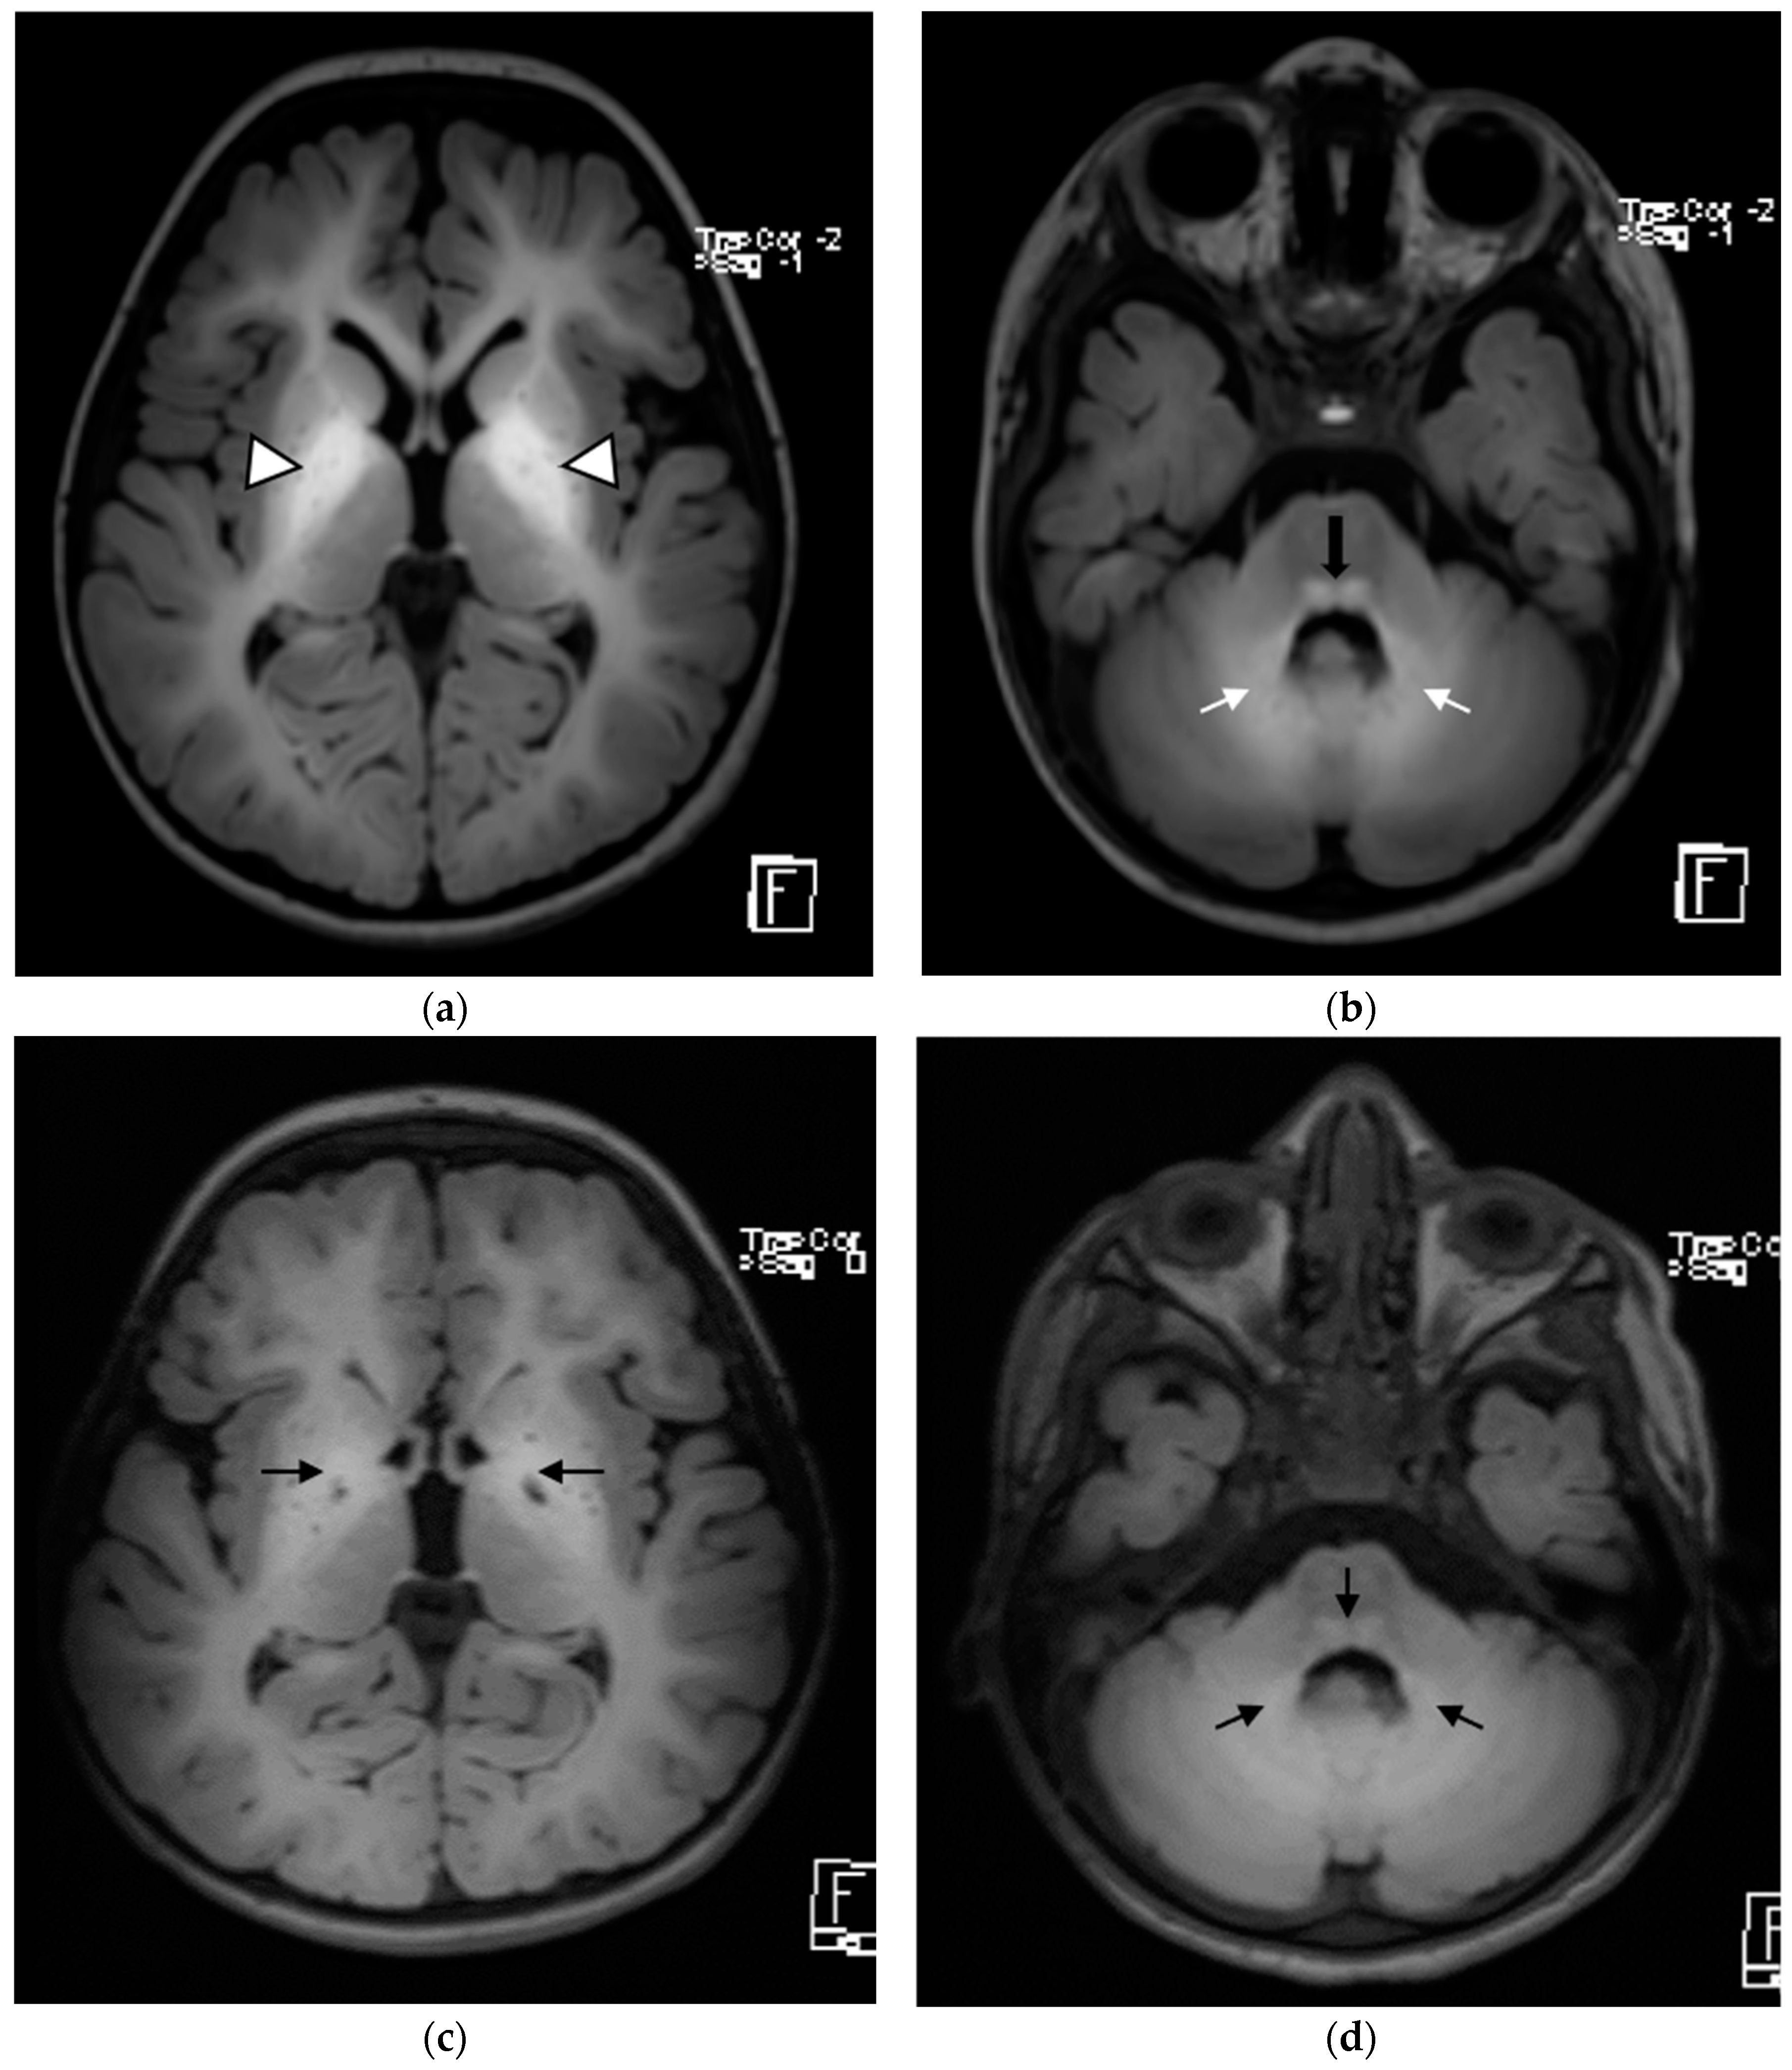

| Brain MRI findings at the time of diagnosis | Symmetrical involvement of the basal ganglia, with decreased T2 and increased T1 signal intensity Mild global atrophy Mildly enlarged eye globes | Symmetrical involvement of the basal ganglia, with decreased T2 and increased T1 signal intensity, and the involvement of cerebellar white matter and posterior brain stem to a lesser degree | Symmetrical involvement of the basal ganglia, tegmentum of the midbrain, posterior tegmentum of the pons, both superior cerebellar peduncles and dentate nuclei, with decreased T2 and increased T1 signal intensity |

| Follow-up brain MRI | Not performed | Similar changes to those observed at initial MRI, with no new lesions and no extension of previous lesions | Similar changes to those observed at initial MRI, with no new lesions and no extension of previous lesions |